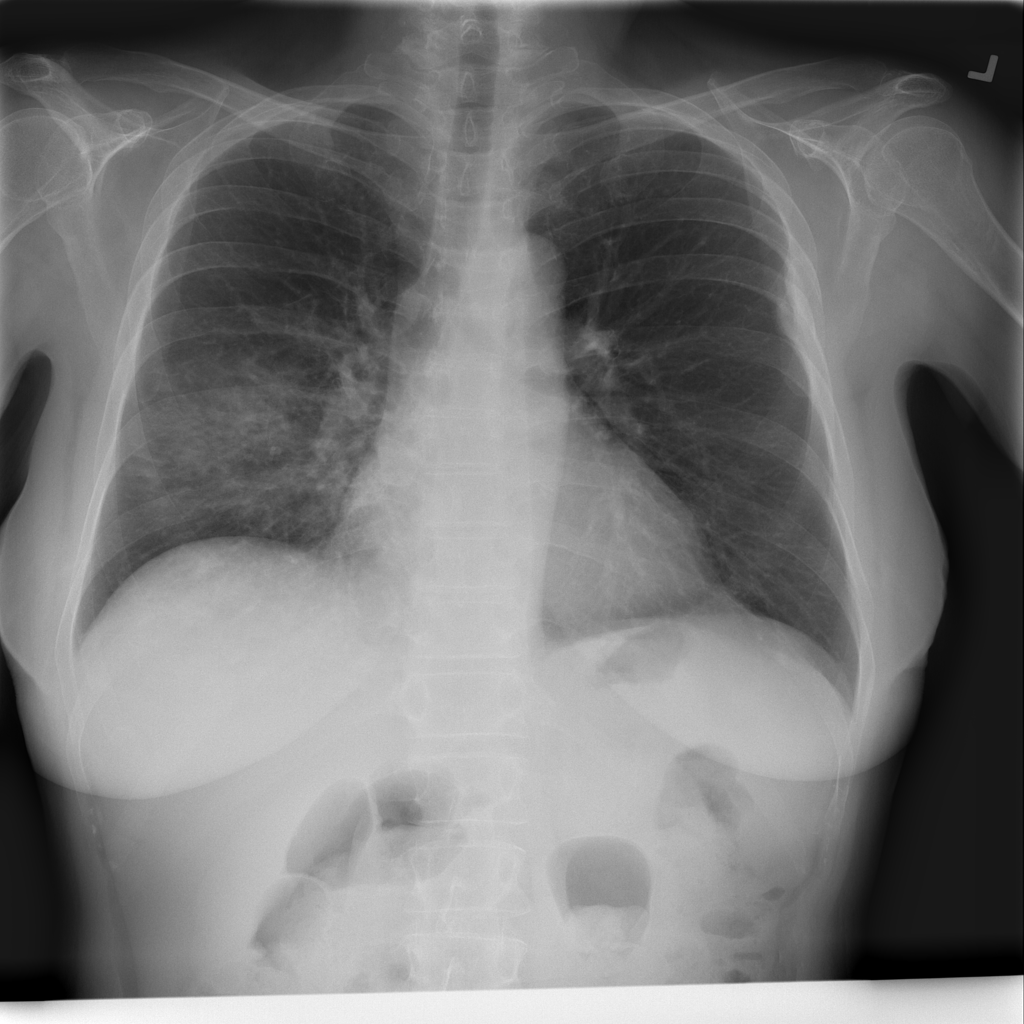

PAT-C0E5 · IMG-015Pneumonia

PAT-C0E5 · IMG-015

AP